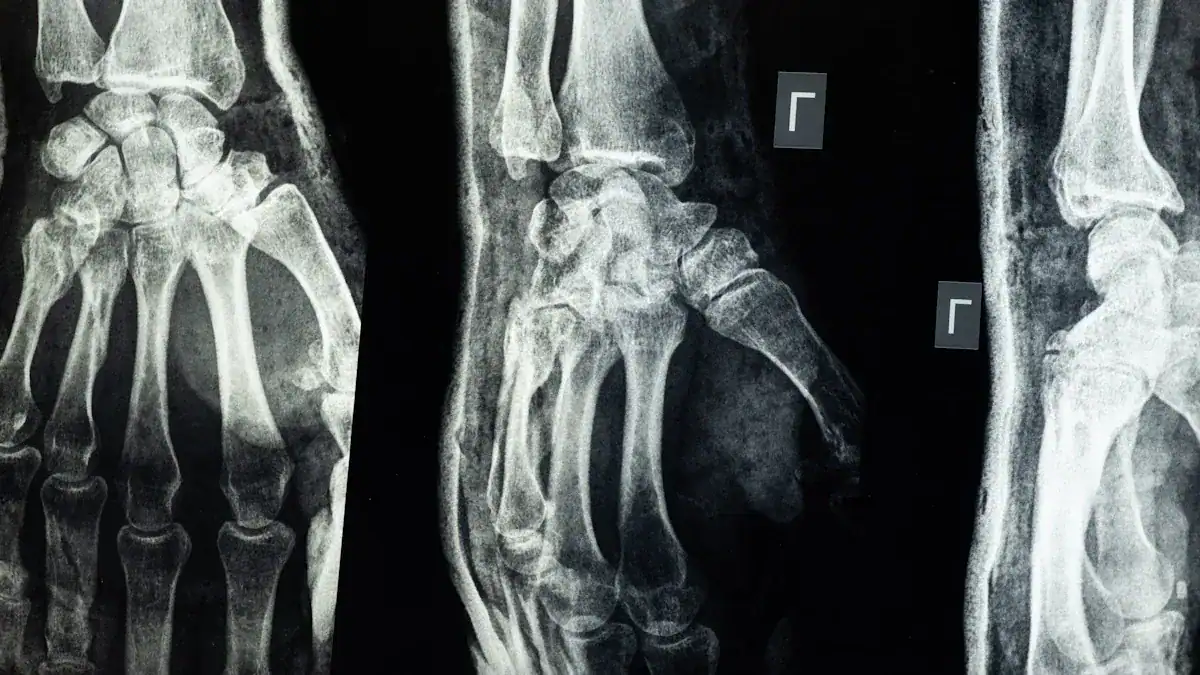

To get a clearer picture, your doctor may order imaging tests. These tests help them see the bones and soft tissues in your wrist. Common tests include:

X-rays: These show bone fractures or arthritis. Sometimes, you need repeat X-rays after 10-14 days.

CT scans: These provide more detailed images of bones.

MRIs: These show soft tissues like ligaments, tendons, and cartilage.

Ultrasounds: These can visualize soft tissues and nerve compression.